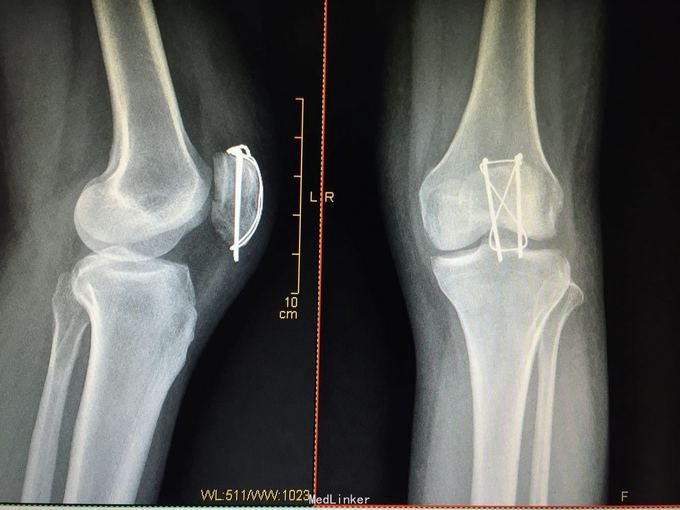

髌骨骨折切开复位克氏针张力带内固定

左髌骨骨折 急诊行切开复位克氏针张力带内固定术

术后1年骨折已愈合、功能良好,予取出内固定。 讨论 髌骨骨折除了经典克氏针张力带,大家还做那些术式及内固定,术后如何行功能锻炼